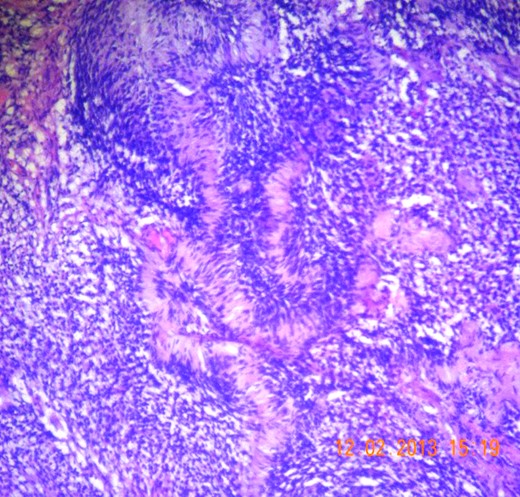

Gross appearance showed 6 × 4 × 4 cm smooth encapsulated right thyroid swelling with a posterior cystic area which was yellowish brown in colour. Walls of the cyst were bright yellow with polypoid areas (Fig. 4). Histology showed classical Antoni A (hypercellular areas) with Verocay bodies and Antoni B (hypocellular) pattern, with interspersed thyroid cells along the periphery (Figs 5–7). The lesion was reported to be arising from within the thyroid gland itself and not extrinsic to it.

Microscopic section (H&E slide, 40×) of Verocay bodies within Antoni A pattern.

Microscopic section (H&E slide, 100×) of magnified view of a region in Fig. 6 showing Verocay bodies.